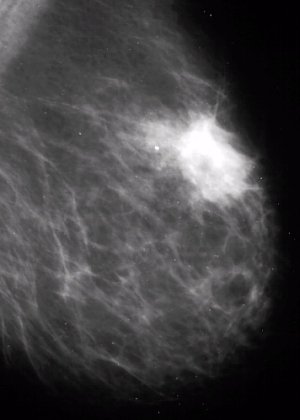

УЗИ молочных желез — информативный и безопасный метод диагностики, с помощью которого можно точно оценить состояние желез, обнаружить доброкачественные и злокачественные образования, уточнить диагноз. Это доступное по цене исследование безвредно и не несет лучевой нагрузки. Оно имеет большое значение в ранней диагностике заболеваний и нередко применяется в профилактических целях. На УЗИ может направить маммолог, онколог, эндокринолог, гинеколог.

Сделать УЗИ молочных желез можно в качестве первичной диагностики и для уточнения уже предполагаемого диагноза. Метод основывается на способности высокочастотных ультразвуковых волн с различной скоростью отражаться от тканей с разной плотностью.

С помощью ультразвуковой диагностики можно обнаружить следующие заболевания:

- воспалительные заболевания — мастит, абсцессы, лактостаз у кормящих женщин, мастопатии различного происхождения и типа — фиброзно-кистозные, диффузные и пр.;

- врожденные аномалии молочной железы;

- рак;

- кисты и доброкачественные опухоли;

кальцинаты.

Для оценки кровотока в тканях молочных желез используется доплерография. Данные, полученные в результате биопсии под контролем УЗ-аппарата, могут сказать о природе и характере образований в молочных железах.

Диагностировать липому может врач хирург после визуального осмотра и пальпации места новообразования. По рекомендации врача может потребоваться УЗИ мягких тканей, маммография или биопсия с цитологическим или гистологическим исследованием.

По рекомендации врача может потребоваться УЗИ мягких тканей, маммография или биопсия с цитологическим или гистологическим исследованием.